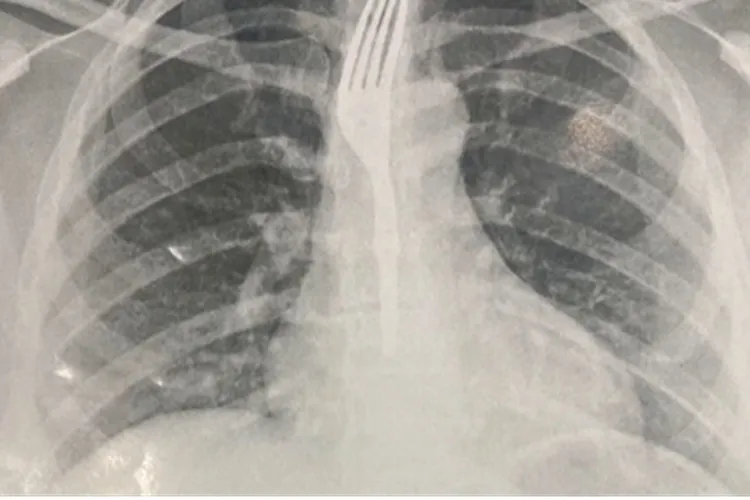

De acordo com informações do Hospital Geral de Guanambi (HGG), a paciente deu entrada na unidade e passou por exames de imagem, que confirmaram que o utensílio estava alojado no esôfago, em uma posição de risco para complicações graves.

Diante do quadro, os médicos avaliaram que seria necessário um procedimento especializado para a retirada segura do objeto. Por isso, a paciente foi transferida para Vitória da Conquista, onde deve passar pela intervenção médica adequada.